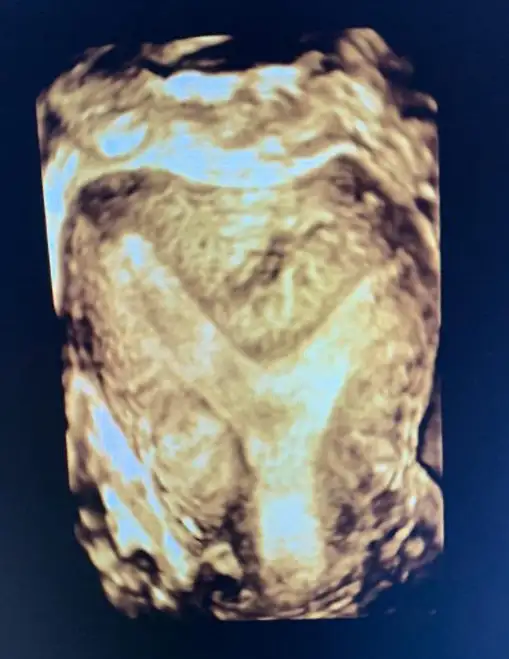

Velhasılı kelam ben de 2 kere düşük yaptım, bu rahim şekliyle gebe kalabilmek oldukça zor iken gebe kalabiliyoruz bu harika. Fakat perdeden dolayı 2 gebeliğimde de 15. Hafta hep düşük yaptım. Histeroskopi oldum, perde alındı. Şuan artık gebeliğimde düşük olmaması gerekiyormuş. Gebe kalabilmeyi bekliyorum.

Sana rahmimin ameliyat öncesi ve sonrasını gönderiyorum fikrin olması açısından